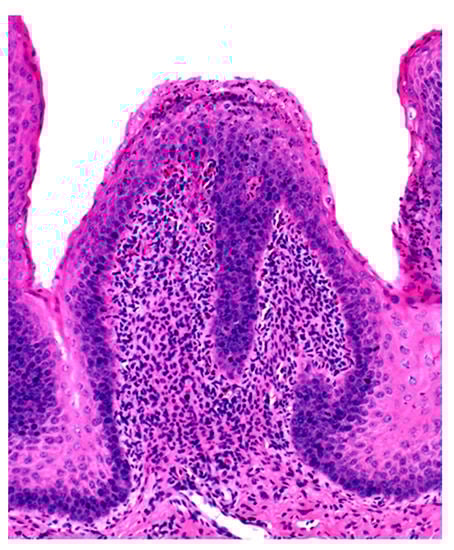

Microscopic changes are usually absent in the rumen of animals dying of acute rumen acidosis, unless pre-existing subacute lesions were present before the onset of acute disease. Microscopic examination of the rumen in cases of sub-acute or chronic acidosis reveals lesions consistent with chemical rumenitis, including enlarged ruminal papillae, cytoplasmic vacuolation of the epithelial cells often leading to vesiculation, and a mild to marked neutrophilic infiltration in the mucosa and submucosa (Figure 2). There may be multifocal erosion and ulceration of the superficial mucosa. Absence of protozoa is consistent with chemical rumenitis, but is also influenced by the interval between death and the postmortem examination. Similar changes may be detected in the other pre-stomachs. Apart from general congestion, there are no specific changes in other organs [18].